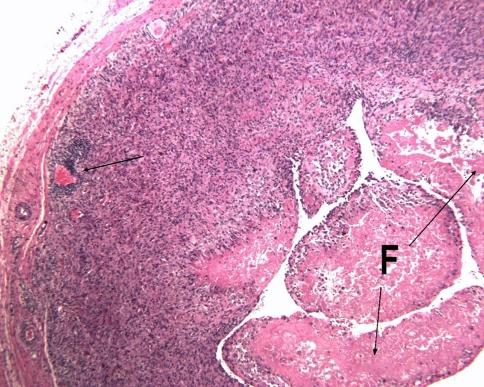

QUESTIONS/PURPOSES: We therefore examined the synovial lining integrity, inflammatory cell infiltrates, tissue organization, necrosis and metal wear particles of pseudotumor-like tissues from M-M hips revised for suspected high wear related and suspected metal hypersensitivity causes.

Tissue samples from 32 revised hip replacements with pseudotumor-like reactions were studied. A 10-point histological score was used to rank the degree of aseptic lymphocytic vasculitis-associated lesions (ALVAL) by examination of synovial lining integrity, inflammatory cell infiltrates, and tissue organization. Lymphocytes, macrophages, plasma cells, giant cells, necrosis and metal wear particles were semiquantitatively rated. Implant wear was measured with a coordinate measuring machine. The cases were divided into those suspected of having high wear and those suspected of having metal hypersensitivity based on clinical, radiographic and retrieval findings. The Mann-Whitney test was used to compare the histological features in these two groups.

The tissues from patients revised for suspected high wear had a lower ALVAL score, fewer lymphocytes, but more macrophages and metal particles than those tissues from hips revised for pain and suspected metal hypersensitivity. The highest ALVAL scores occurred in patients who were revised for pain and suspected metal hypersensitivity. Component wear was lower in that group.

Pseudotumor-like reactions can be caused by high wear, but may also occur around implants with low wear, likely because of a metal hypersensitivity reaction. Histologic features including synovial integrity, inflammatory cell infiltrates, tissue organization, and metal particles may help differentiate these causes.